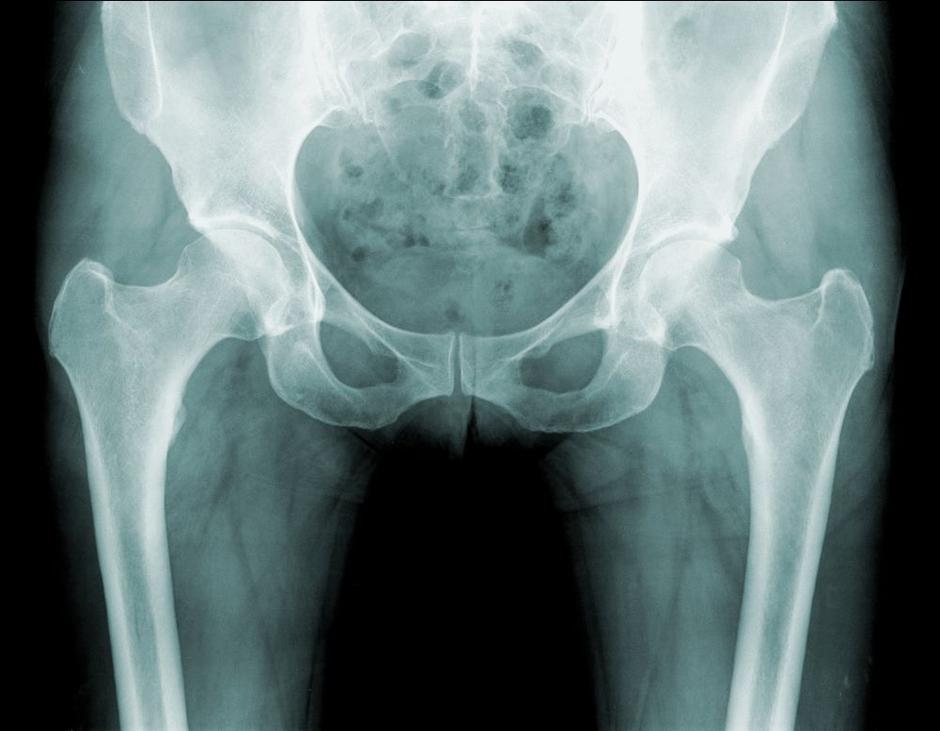

Strokovna fizioterapija lahko bistveno pripomore k izboljšanju funkcionalnosti kolčnega sklepa, zmanjšanju bolečin in povečanju kakovosti življenja. Tukaj so stanja, ki zahtevajo rehabilitacijo kolka:

• Artroza kolka (degenerativna bolezen sklepov): Zmanjšanje bolečin in izboljšanje gibljivosti sklepa.

• Femoroacetabularna utesnitev (FAI): Zdravljenje omejene gibljivosti in bolečine, ki nastanejo zaradi nepravilne oblike kosti kolčnega sklepa.

• Displazija kolka: Rehabilitacija za posameznike z nepravilnim razvojem kolčnega sklepa, ki lahko vodi do bolečin in nestabilnosti.